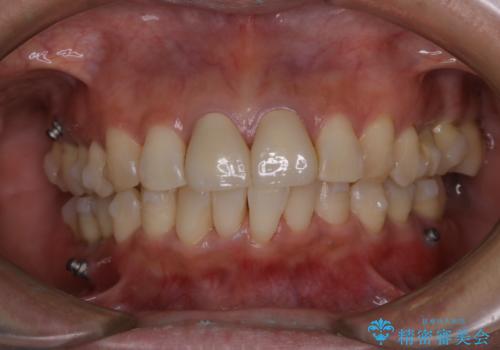

- インビザラインでのマウスピース矯正中の方です。矯正中にも定期的なクリーニングを希望とのことでした。PMTC30分コースを行いました。

マウスピース矯正インビザライン治療では、歯の表面にアタッチメントという突起を設定します。(アタッチメントは歯の動きを効率的に移動するためのものです)

アタッチメントが歯に付くと、表面が凸凹し磨き残しが多くなったりと、プラークや歯石・着色がつきやすくなることがあります。